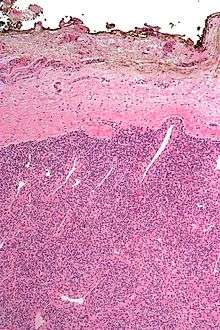

A resection margin is the margin of apparently non-tumerous tissue around a tumor that has been surgically removed, called "resected", in surgical oncology. The resection is an attempt to remove a cancer tumor so that no portion of the malignant growth extends past the edges or margin of the removed tumor and surrounding tissue. These are retained after the surgery and examined microscopically by a pathologist. If cancerous cells are found at the edges the operation is much less likely to achieve the desired results.[1]

Apart from traditional methods looking at stained "shaves" (thin slices of tissue removed from the edge of the margin) or smeared and stained imprints, more recent techniques used to assess margins include x-rays with compression, frozen specimens, and new techniques such as optical coherence tomography and quantitative diffuse reflectance spectroscopy.[4]